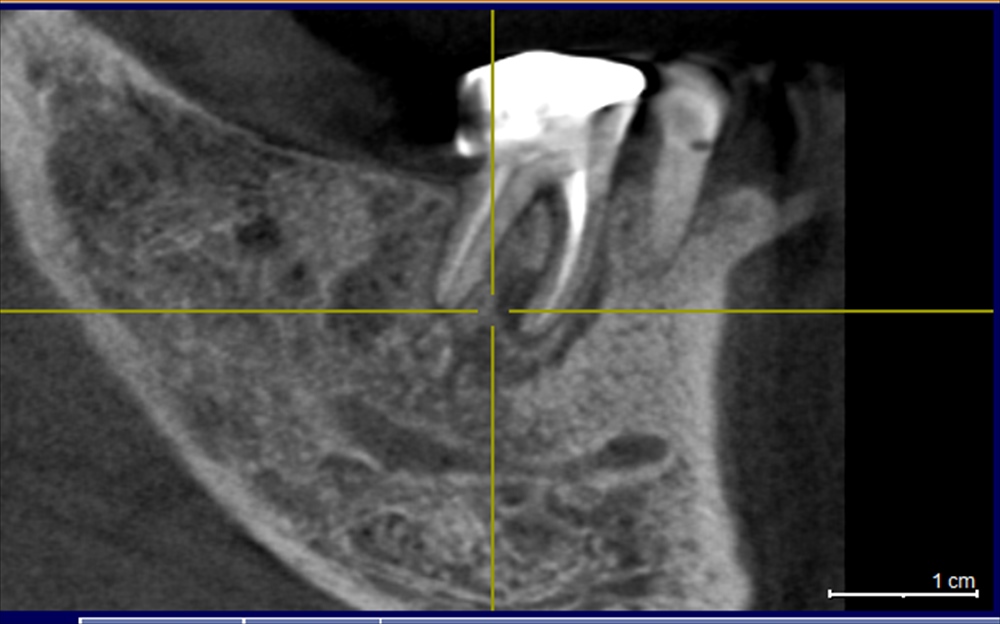

丁度1年前。17年5月21日

ご覧の通り根の周りは骨が全くなくグラグラ。右で全く噛めませんでした。

精密根管治療を1年前に施し